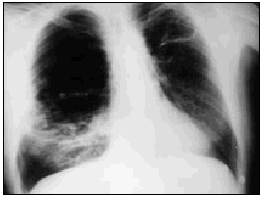

Varón de 60 años, diabético y con insuficiencia respiratoria crónica por enfisema pulmonar que ingresa por una neumonía en el lóbulo medio derecho. Se inició tratamiento con broncodilatadores inhalados, una cefalosporina de tercera generación y un macrólido, con mejoría inicial. En la tercera semana, ante la persistencia de cuadro febril, se realizó una radiografía de tórax (fig. 1) en la que se observa un infiltrado en el pulmón derecho de gran tamaño y con nivel hidroaéreo, por lo que se le añadió un antibiótico anaerobicida. En una TC torácica se observaba la lesión ya conocida (fig. 2. flecha izquierda) y otra pequeña imagen redondeada, con nivel hidroaéreo en su interior, en el espacio prevascular (fig. 2. flecha derecha). El fluido contenido en la lesión mayor era más denso que el agua y tenía burbujas de gas en su interior (fig. 2 punta de flecha). En un cultivo de esputo se cultivó Pseudomonas aeruginosa multisensible. Tras un acceso de tos, en una nueva radiografía de tórax (fig. 3) desaparece el infiltrado derecho, diseminándose la infección pulmonar, falleciendo el paciente días después en situación de shock séptico. Se estableció el siguiente diagnóstico: bullas pulmonares infectadas; bronconeumonía bilateral por P. aeruginosa.